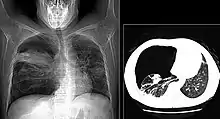

The diagnosis can be confirmed by the characteristic appearance of the chest X-ray and an arterial oxygen level (PaO2) that is strikingly lower than would be expected from symptoms. Gallium 67 scans are also useful in the diagnosis. They are abnormal in about 90% of cases and are often positive before the chest X-ray becomes abnormal. Chest X-ray typically shows widespread pulmonary infiltrates. CT scan may show pulmonary cysts (not to be confused with the cyst-forms of the pathogen).

Chest X-ray demonstrating bilateral pulmonary infiltrates caused by pneumocystis pneumonia.